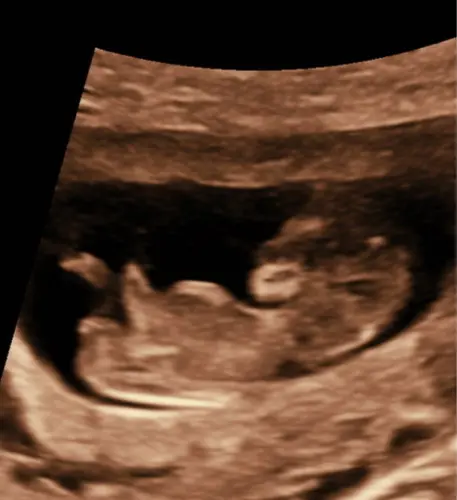

Hoi hoi! Hier 13+4 zwanger en vandaag 13 weken echo gehad. Dit is de enige foto van de zijkant want ons kindje was steeds aan het draaien haha. Heel benieuwd of jullie iets kunnen zien. Groetjes!

Hoi hoi! Hier 13+4 zwanger en vandaag 13 weken echo gehad. Dit is de enige ...